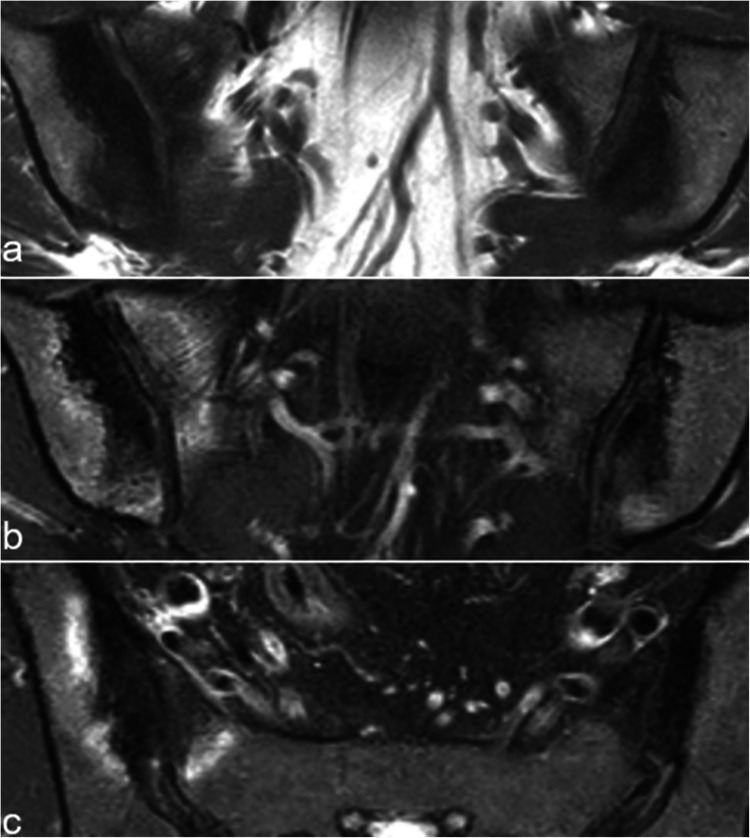

Magnetic resonance imaging of the sacroiliac joints (SIJ) is now frequently performed to detect subchondral inflammatory and structural changes in patients with early axial spondyloarthritis (SpA). However, similar changes can also occur in various other conditions, which may lead to the overdiagnosis of axial SpA. The aim of this article is to review the key imaging features of the most common disorders that may mimic inflammatory sacroiliitis, including mechanical changes and osteoarthritis, osteitis condensans ilii and pregnancy-related changes, other strain related changes, anatomical variants, pediatric SIJs, hyperostosis, infectious sacroiliitis, SAPHO syndrome, hyperparathyroidism, and sacral stress fractures.